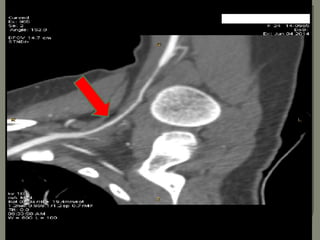

 Arterial doppler of left

upper Limb Shows

stenosis of the left

subclavian artery with

diminished flow

beyond

Ultra Sound Doppler 6th May

2014:

Show stenosed left subclavian

artery with diminished flow

beyond and normal flow in rt

arm